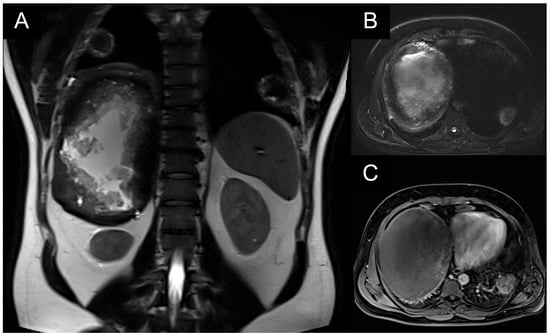

These were addressed synchronously with bilateral posterior thoracotomies in a prone position, using our experience in bilateral lung transplantation with this approach (left side: through the VII left intercostal space; right side: through the VI right intercostal space). Gentle manual palpation is necessary for localization. Wedge-type excisions were performed using standard automatic endostaplers of 45/60 mm length on clear macroscopic margins of minimum 1 cm interval (Figure 3). Histopathological confirmed extensive tissue necrosis and echinococcal structures (Figure 4). The parasite lesions may extend directly across the diaphragm and their rupture is a respiratory emergency.

Figure 11. An intraoperative image of patient 3. Extensive dissection is required to remove the echinoccocal lesion and the surrounding necrotic tissue, leaving a raw parenchyma and frequently open segmental and subsegmental bronchi. Bronchial openings (yellow arrows) must be ligated for aerostasis. Endostaplers are not advised for this situation. We advise the use of absorbable sutures to ligate open ends and approximate raw surfaces.